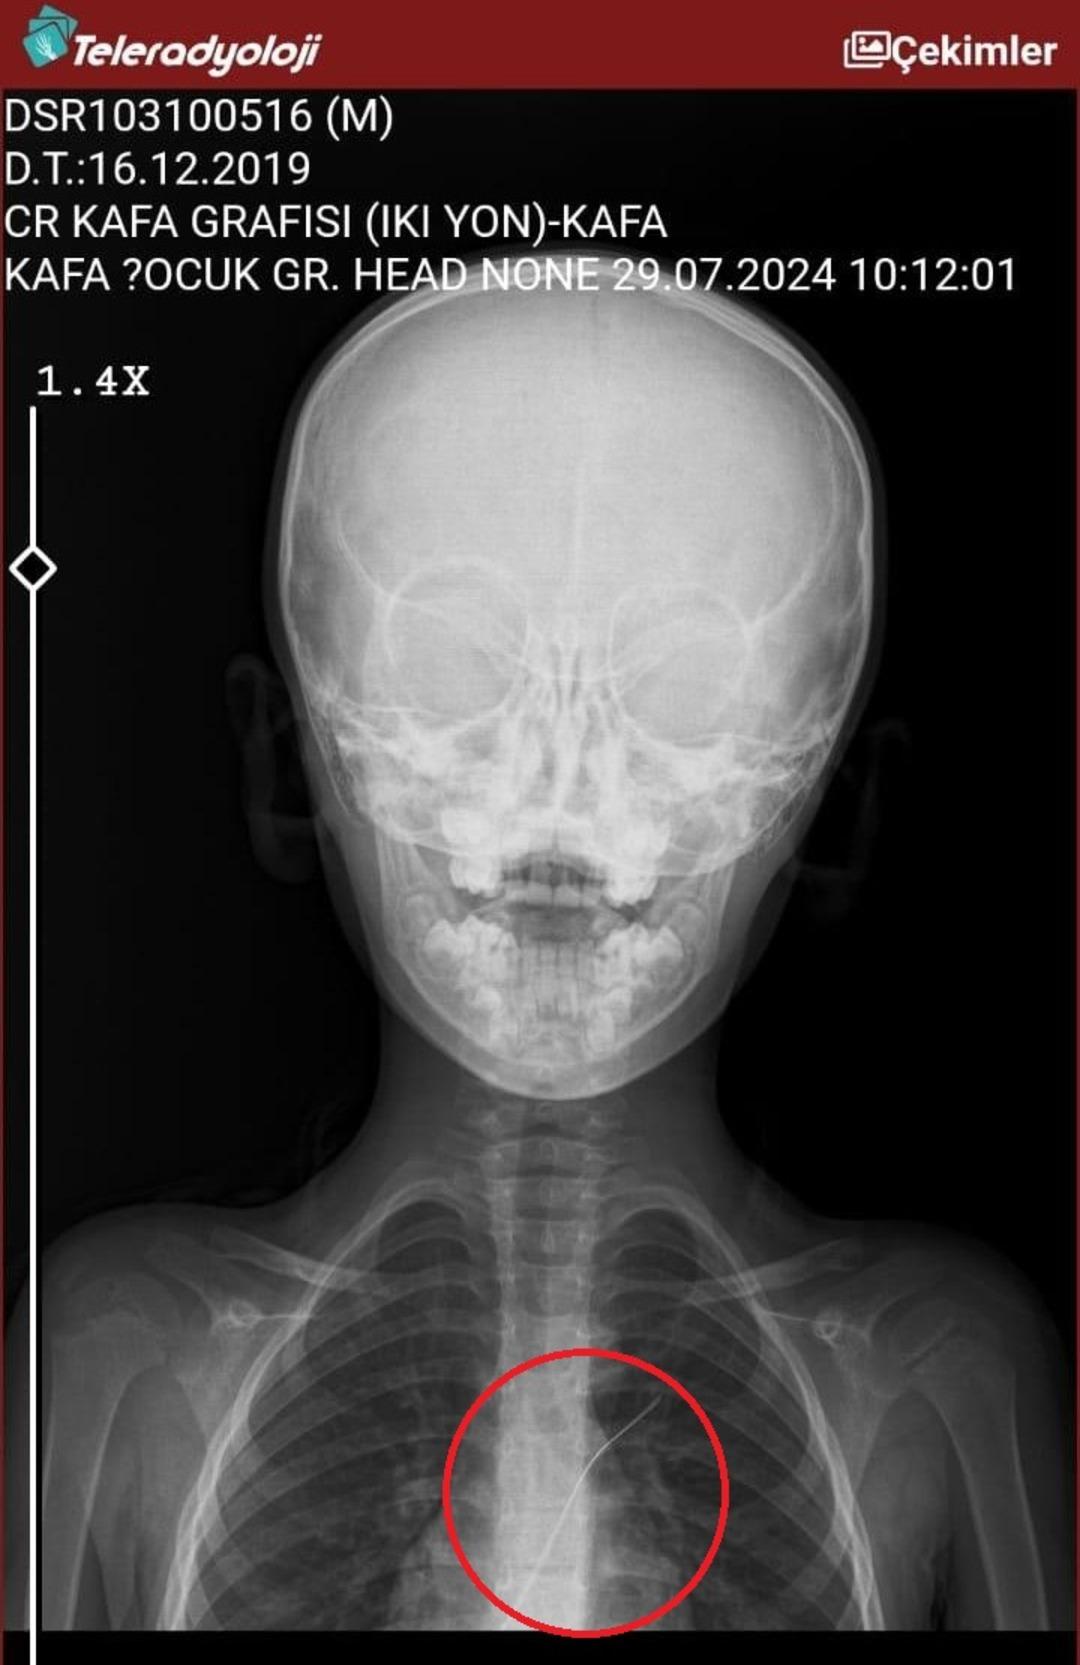

Seamore (37) ve Şaç'ta yaşayan Mehmet Ötün (40), Mayıs ayında bir parça salatalık yuttuktan sonra öksürük ve kusma şikayetleri gözlendiğinde Sernak Eyalet Hastanesine getirildi. Burada, ARAM gövdesinde yarıçap X ve manyetik rezonans görüntüleme unutuldu. Diyarbakir Gazi Yeşargil'in eğitim ve araştırma hastanesi jinekolojiye ve ARAM'lar için ek binaya yönlendirildi, 18 santimetrede 5.5 saatlik riskli cerrahi kaldırıldı. Postoperatif araştırmalarda, kateter kalp kapakına ve karaciğere zarar vermeye kararlıydı.